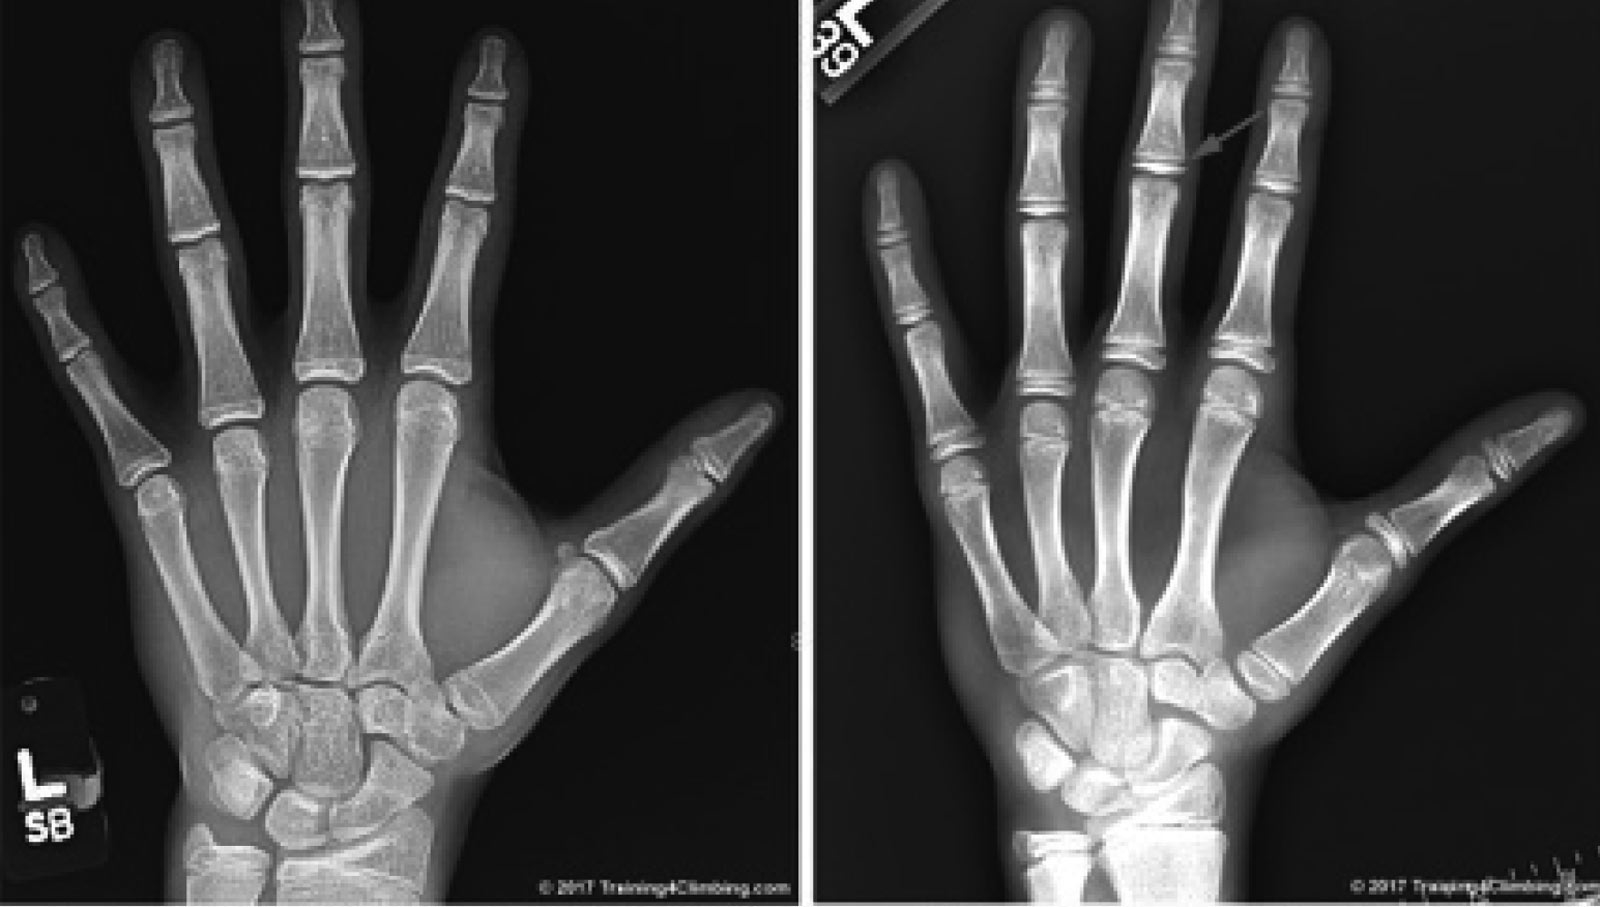

RØNTGEN: Bildet til høyre viser de vidåpne epifyseplatene hos en 14-åring, til venstre kan man se hvordan de er sammenvokst hos en ferdigutviklet 16-åring1. Foto: Training for climbing – Eric Horst

Når barn vokser forlenger skjelettet seg ved hjelp av vekstplater i leddene (epifyseplate). Denne vekstplaten er skjør og tåler ikke like mye belastning som resten av skjelettet. I enkelte faser i livet har kroppen det som kalles en akselerert vekstfase eller vekstspurt, da er disse platene ekstra følsomme for belastning, på røntgenbilder fremstår de som åpninger.

Fasen i livet hvor unge har akselerert vekst og åpne epifyseplater, sammenfaller med puberteten og topper seg statistisk for jenter i 11-årsalderen og gutter i 13-årsalderen. Dette vil selvsagt ha store individuelle forskjeller, men i denne fasen av livet er det størst risiko for skader i dette området.